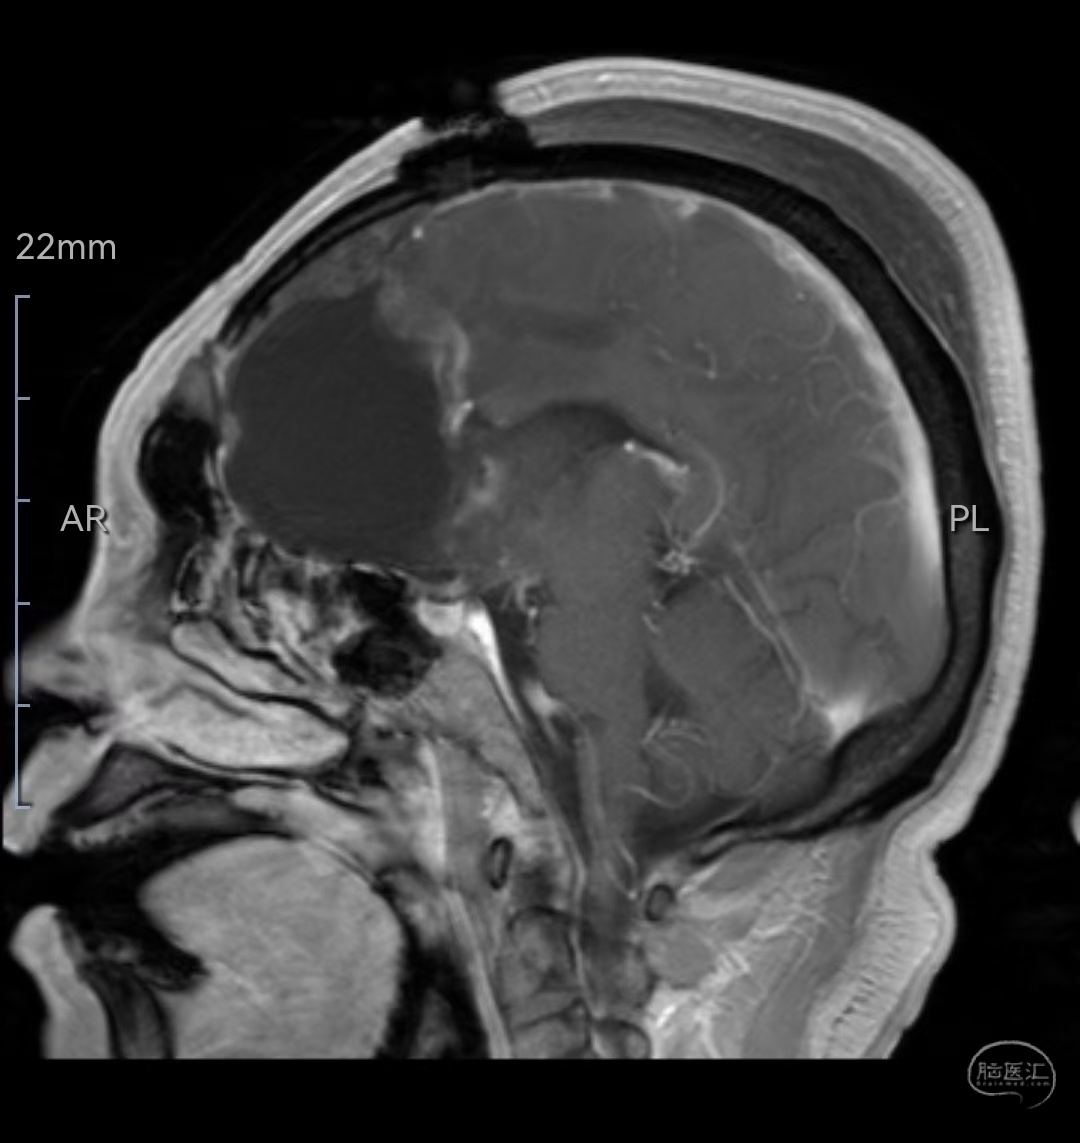

MRI增强矢状位示肿瘤明显强化,侵犯压迫至胼胝体嘴、膝部

MRI增强矢状位示肿瘤全切除,毗邻脑组织保护满意